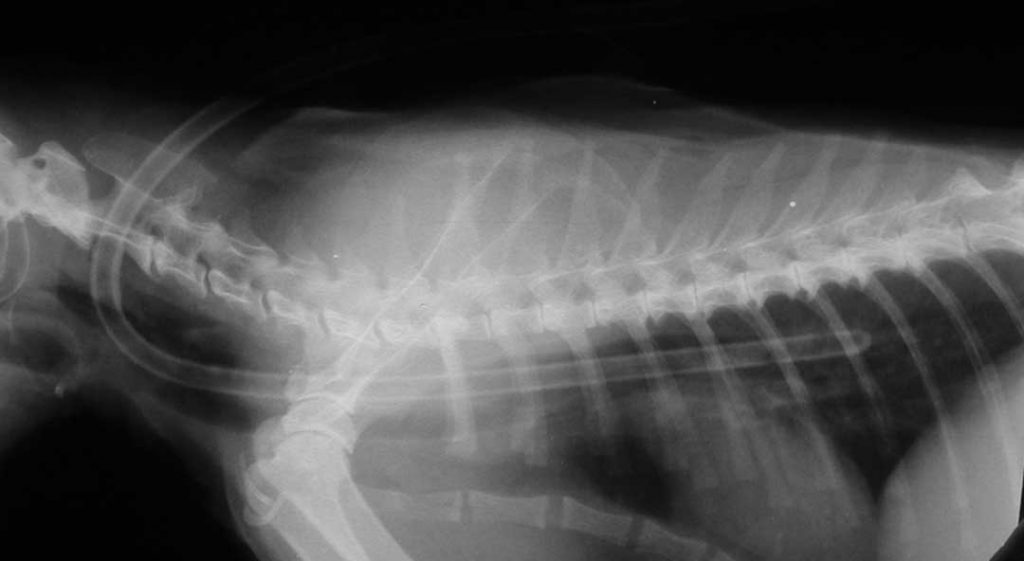

An x-ray reveals the path of the tube. The arrows on top outline the tube that is outside of the neck and under the bandage and along the back. The arrows on the bottom are the feeding tube as it passes inside the esophagus from left to right.

As planned, it goes partway down the esophagus and does not enter the stomach. The white structure just below and to the right of the tube in the esophagus is the heart. The tube never touches the heart because it stays in the esophagus.

Here is another view in larger size, with the tube in the proper location in the esophagus